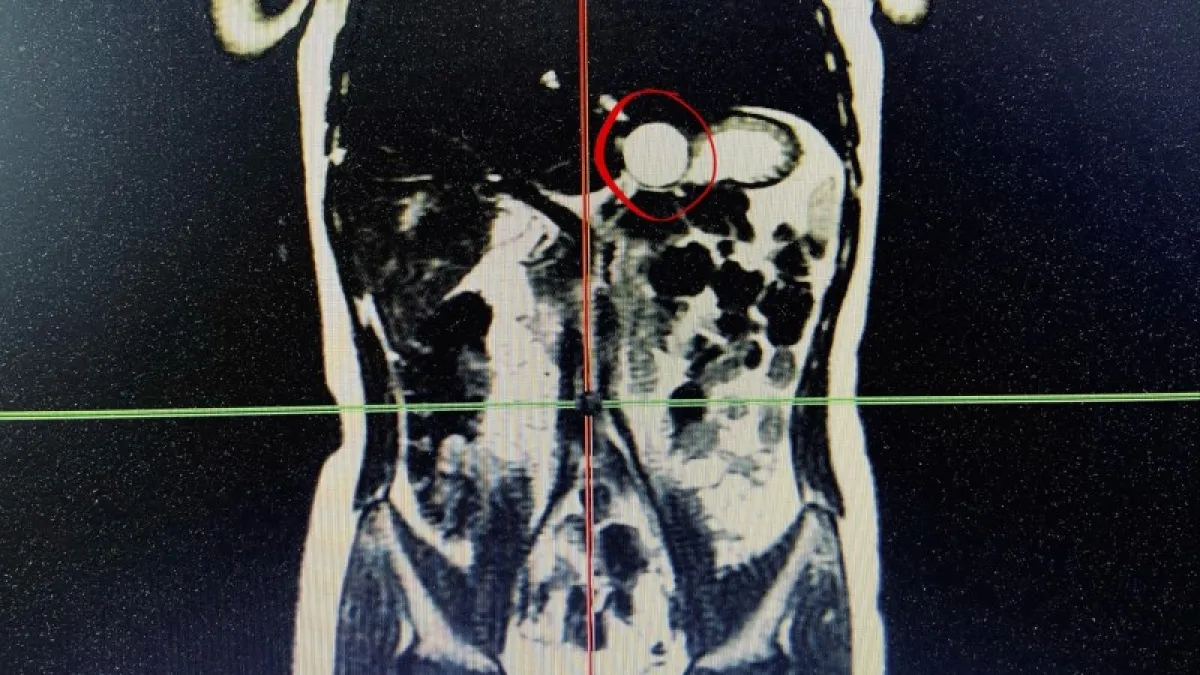

В ходе ультразвукового исследования, проведённого в рамках диспансеризации, у юной пациентки обнаружена кистозная аномалия развития желудочно-кишечного тракта. Это редкое врождённое состояние, при котором в стенке желудка формируется дополнительная полость, изолированная от основного органа. После всестороннего обследования, включая компьютерную томографию, врачи диагностировали необходимость операционного удаления образования.

Как пояснил главный детский хирург Минздрава Коми Руслан Ислентьев, киста диаметром около трёх сантиметров располагалась в критической зоне: на границе пищевода и желудка.